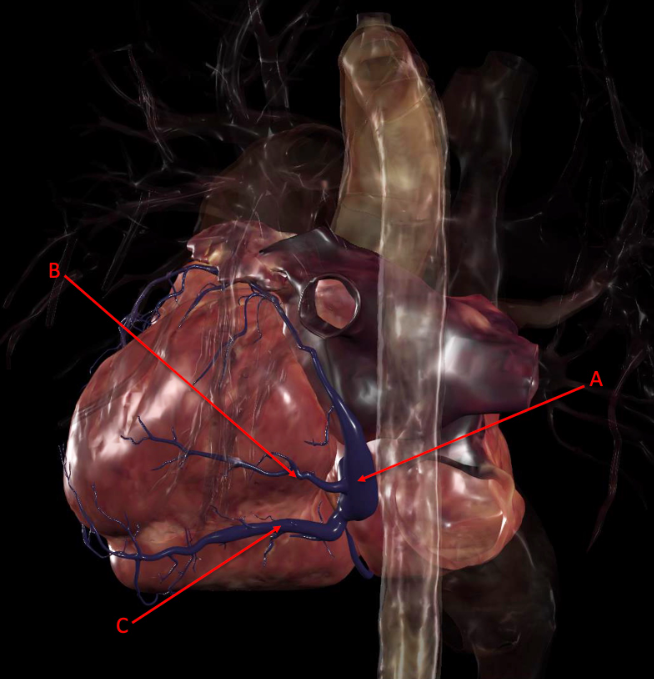

A. coronary sinus

B. Posterior vein of left ventricle

C. middle cardiac vein